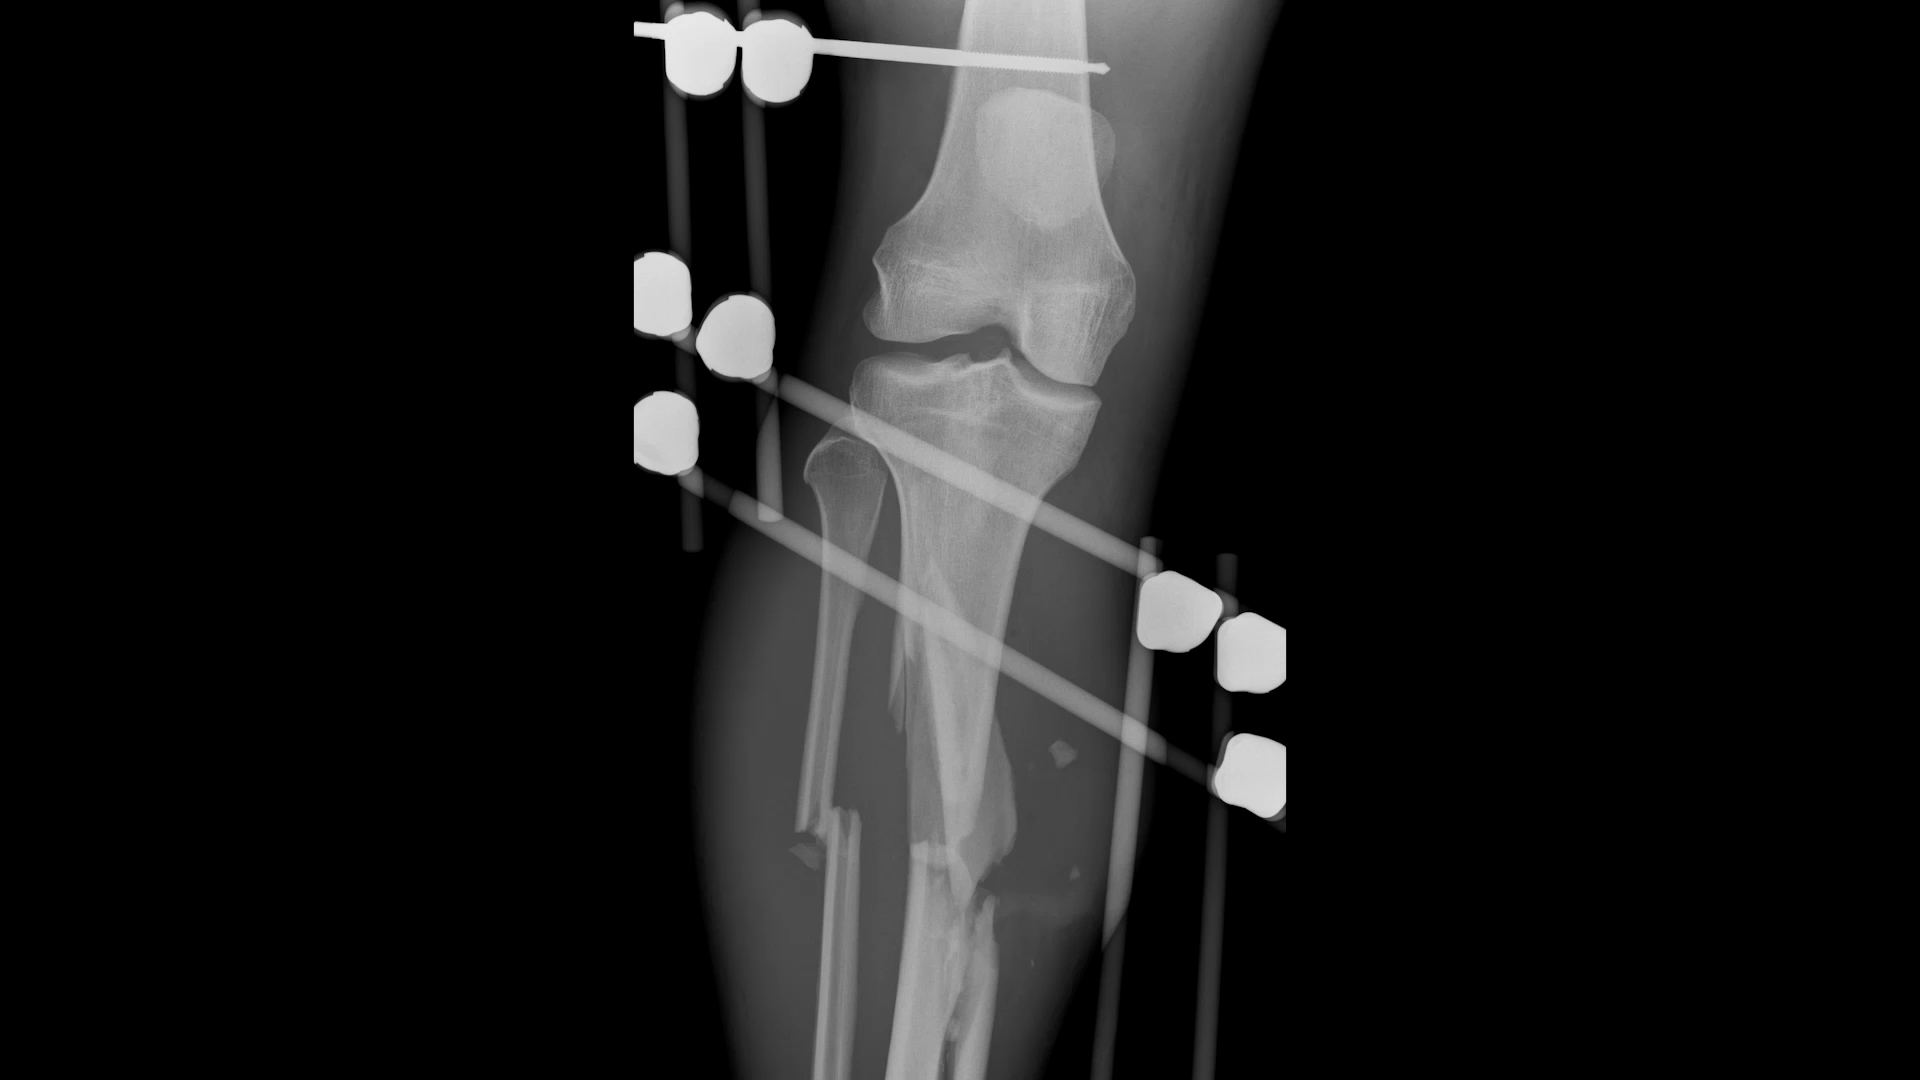

Filmed over six years, No Doubt is the gritty, intimate story of British sprinter James Ellington, whose Olympic dream was shattered in 2017 by a near-fatal motorbike accident. Told he would never walk properly again—let alone run—James defied medical advice and made a bold public declaration from his hospital bed: he was coming back, targeting the 2020 Tokyo Olympics.